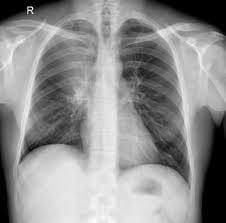

See full list on mayoclinic.org Atelectasis is a lung condition that happens when your airways or the tiny sacs at the end of them don't expand the way they should when you breathe. Confinement to bed with infrequent changes of position 4. Mucus in a collapsed lung may lead to infection. If you're scheduled for surgery, talk with your doctor about strategies to reduce your risk. See full list on hopkinsmedicine.org Using surgery or medicine, doctors can remove the source of the pressure. Evidence for the efficacy of most treatments for atelectasis is weak or absent. Pneumonia.your risk for pneumonia continues until the atelectasis goes away. Treatment depends on the cause and severity of the collapse. Any condition that makes it difficult to swallow 3. Treatment of atelectasis depends on the cause. Medications that may cause shallow breathing 9.